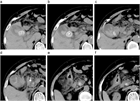

1. 急性胆嚢炎の原因の90~95%は胆嚢結石であり、結石の嵌頓による胆嚢管閉塞と胆嚢内胆汁うっ滞に引き続き、胆嚢粘膜障害が起こり、炎症性メディエーターの活性化が引き起こされる。